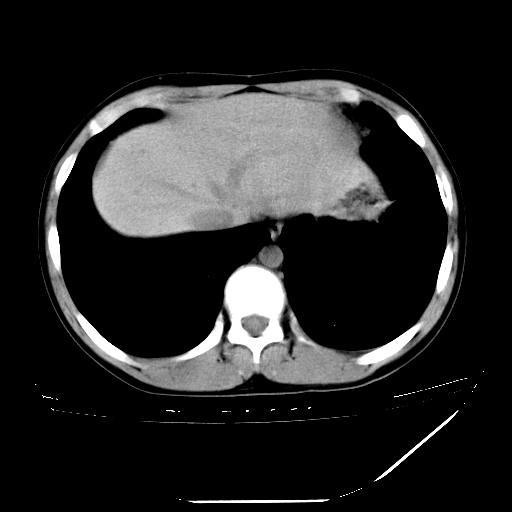

男,13岁,咳嗽、咳痰伴发热一周。

纵隔多发肿大淋巴结,部份有融合改变。双肺血管气管束增厚,以肺门为中心向外周散发,以左肺下叶为明显。考虑淋巴瘤可能性大。不除外原发综合征。

左肺野见淡片状影,病因整体多考虑结核

单纯看片子感觉左侧肺通气不畅,而不像肺内病变引起的纵隔病变。而且纵隔及左肺门都有淋巴结增大。首先还是考虑一下结节病,不排除淋巴瘤!!!